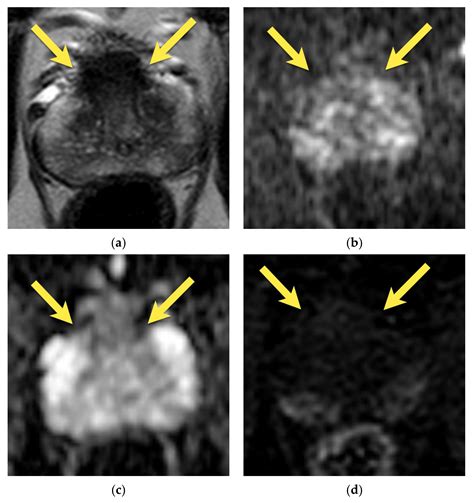

The diagnostic process typically involves three specific sequences that make up the "multi-parametric" aspect of the scan:

• T2-Weighted Imaging: Provides high-resolution anatomical details of the prostate structure.

• Diffusion-Weighted Imaging (DWI): Measures the movement of water molecules in the tissue, which is often restricted in malignant tumors.

• Dynamic Contrast-Enhanced (DCE) Imaging: Monitors how a contrast agent flows into the tissue, helping to highlight areas with abnormal blood vessel growth typical of cancer.

Understanding these scores is crucial for patients, as a PI-RADS 4 or 5 score will almost always lead to a recommendation for a biopsy to confirm the diagnosis and determine the appropriate course of treatment.